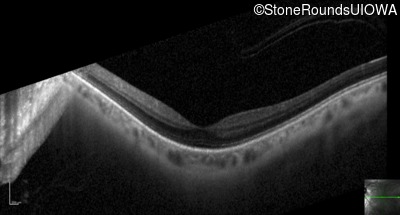

Optical Coherence Tomography - Left - 20/25 +2

Exemplar / OCT Stack